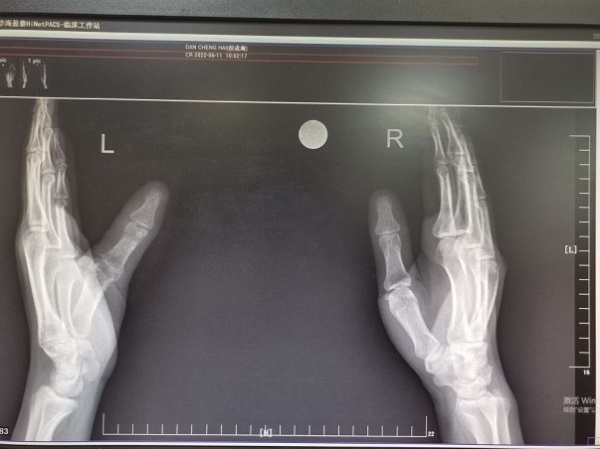

但师傅3个月前左拇指受伤,因左拇指掌指关节毁损,在二一五医院手·显微外科行左拇指掌指关节融合手术,伤口愈合后出院。近期,但先生因左拇指活动受限,影响手指功能,再次来到科室就诊,以“左拇指掌指关节毁损术后”收治入院。入院后,蒋宏魁主任和任锴副主任为其制定了详细的手术方案,第一时间联系厂家进行个性化假体定制。

手术不仅仅要进行关节置换,同时因第一次受伤时指神经受损出现继发性神经瘤,手术操作复杂,需在关节置换前进行神经探查移植修复术,在蒋宏魁主任团队的细致操作下,历时近2小时,手术顺利完成。